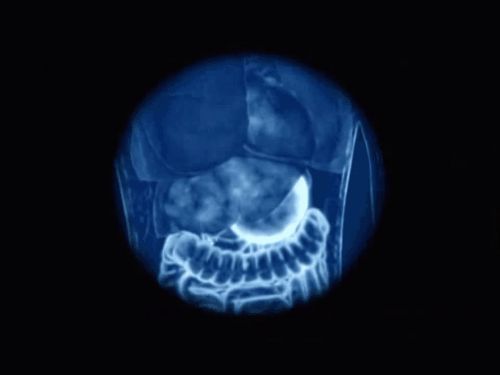

Hệ thống tiêu hóa của bạn được tạo thành từ năm phần chính:

- Miệng

- Thực quản

- Dạ dày

- Ruột non

- Ruột già